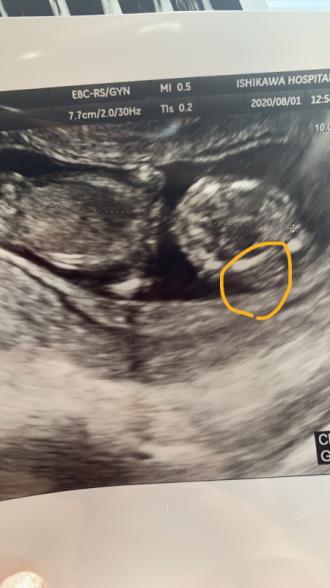

現在私が31歳。妊娠13週ですが、先週の土曜日の検診の際に、『赤ちゃんの頭の一部に浮腫がある。リンパ管の浮腫みや、染色体異常の可能性も考えられる。来週また検診へ来てください、旦那さんは連絡付きますか?電話させてもらうかもしれない。』と言われました。また、身体全体の大きさも2週間ほど小さいようです。 不安になり、ネットで調べてみると、首の後部浮腫はよく出てくるのですが、頭の浮腫はなかなか出てこず困惑しています。赤ちゃんにどのような事がおこっているのでしょうか。。ちなみに浮腫は1.5ミリか1.5センチかどちらかです…動揺していて単位が分からなくなってしまいました。ダウン症や18トリソミーの疑いもなくはないでしょうか。写真から何か分かることはありますか?

昨日、検査に行きましたところ、赤ちゃんの成長とともに頭部の膨らみも大きくなっていました。脳瘤の恐れがあるとの事でした。珍しい事のようです。

ただ、昨日観て頂いた先生は専門医ではない為、断言は出来ないので、来週脳神経に詳しい医師(普段は大学病院勤務されている方)がいらっしゃる日に再度検査(エコーと超音波)となり、その後大学病院で再度検査していく方向との事でした。